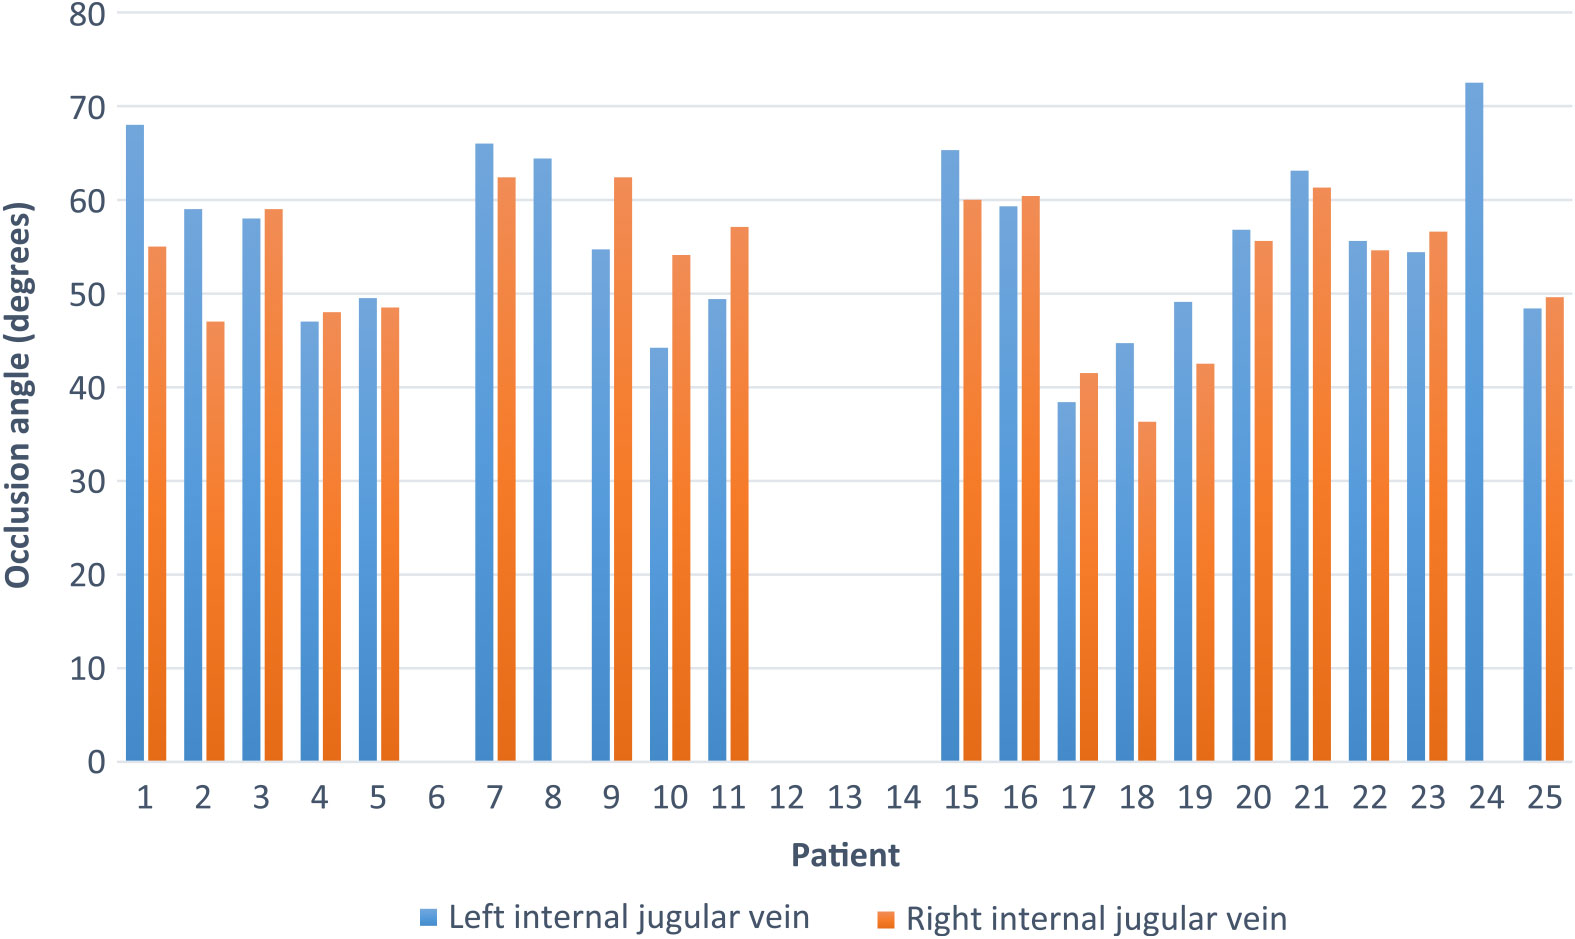

Twenty-five patients (15 male and 10 female) were studied. Inclusion criteria included any patient requiring general anesthesia and presenting for any surgical procedure except those of the head/neck and thorax. Surgical procedures are shown in Table 1. All patients followed standard fasting recommendations and clear fluids were encouraged up to 2 hours prior to surgery consistent with an institutional protocol. Exclusion criteria included previous surgery, radiation, or central line placement due to potential anatomical distortion and/or scarring, and any pathology that could result in significant fluid shifts or cardiorespiratory disease that could alter venous drainage into the right atrium (such as tricuspid stenosis). Patient demographic information included an average age of 52.8 years, average weight of 82.4 kg, average body mass index of 28.9, and average height of 171.2 cm. On a left head turn, 21/25 (84%) IJ veins occluded at an average head turn of 55.6° (range, 38.4–72.5). On a right head turn, 19/25 (76%) IJ veins occluded at an average head turn of 53.3° (range, 36.3–62.4). Of those that did not occlude, 4 patients did not occlude their IJ vein on both sides (patients 6, 12, 13, and 14), and 2 patients did not occlude their right IJ but did occlude their left IJ (patients 8 and 24). These data are shown in Figure 1. Figure 2 demonstrates representative ultrasound images obtained during this study. All patients demonstrated a patent contralateral IJ vein when occlusion or maximal neck rotation was established.

Figure 1: Occlusion angle of right and left IJ vein by patient. Patients without data did not occlude the respective IJ with maximal head rotation.